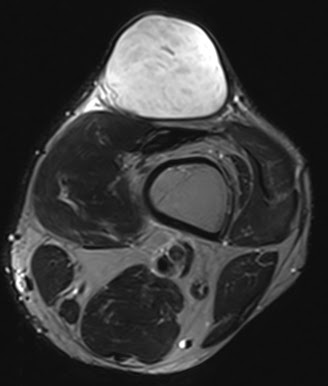

При осмотре атерома представляет собой опухолевидное образование округлой формы, мягкой консистенции размером от 5 до 40 мм и более. Кожа над атеромой обычно не изменена, однако в случае присоединения воспаления может иметь красноватый оттенок. Атерома подвижна вместе с окружающими тканями, безболезненна. Атерома может оставаться маленькой на протяжении многих лет, либо увеличиваться.

Иногда атерома сообщается с поверхностью кожи через небольшое отверстие, через которое могут отделяться атероматозные массы. Часто атеромы нагнаиваются, кроме этого, может происходить разрыв атеромы в подкожную клетчатку.